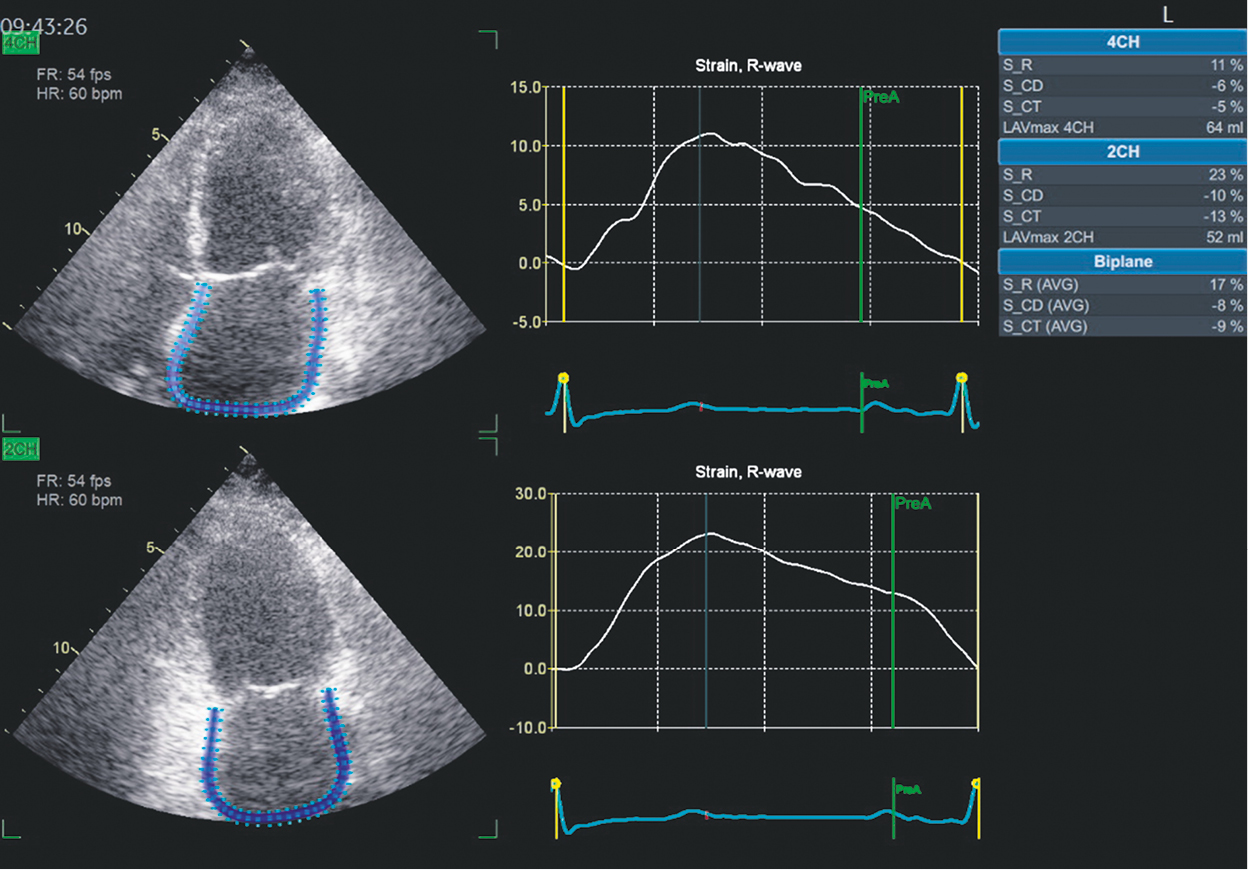

In consideration of the notable LA dilatation, LA function was evaluated in the longitudinal strain mode (2D strain) (Fig. 3). As in the case of longitudinal LV myocardial strain, LA myocardial strain parameters were abnormal. The deformation index during the reservoir phase was equal to 13% (with a mean normal value of 39%, 95% confidence interval [CI] 38%–41%). During the conduit phase, it was 5% (with a mean normal value of 23%, 95% CI 21%–25%), whereas during the contractile phase, it was 8% (with a mean normal value of 17%, 95% CI 16%–19%) [6]. Notably, the strain indices during the conduit and contractile phases were negative, as the LA myocardium shortens during these phases. For the convenient comparison of indices, it is customary to discard the minus sign. In our patient, the LA function during all three phases was significantly impaired. Because the assessment of LA myocardial strain was performed for the first time, it was not possible to ascertain the extent to which LA function had been disturbed previously.

Fig. 3. Assessment of left atrial function in 2022 in 2D-Strain mode. Explanation in the text

In addition to LV diastolic function improvement, the LA volume tended to decrease (Fig. 4). Indices of LA function have improved. Consequently, the proportion of LA myocardial strain increased from 13% to 17% during the reservoir phase, from 5% to 8% during the conduit phase, and from 8% to 9% during the contractile phase. The dynamics of the indices are presented in Table 3.

Fig. 4. Assessment of left atrial function over time in February 2024 in 2D-Strain mode. Explanation in the text